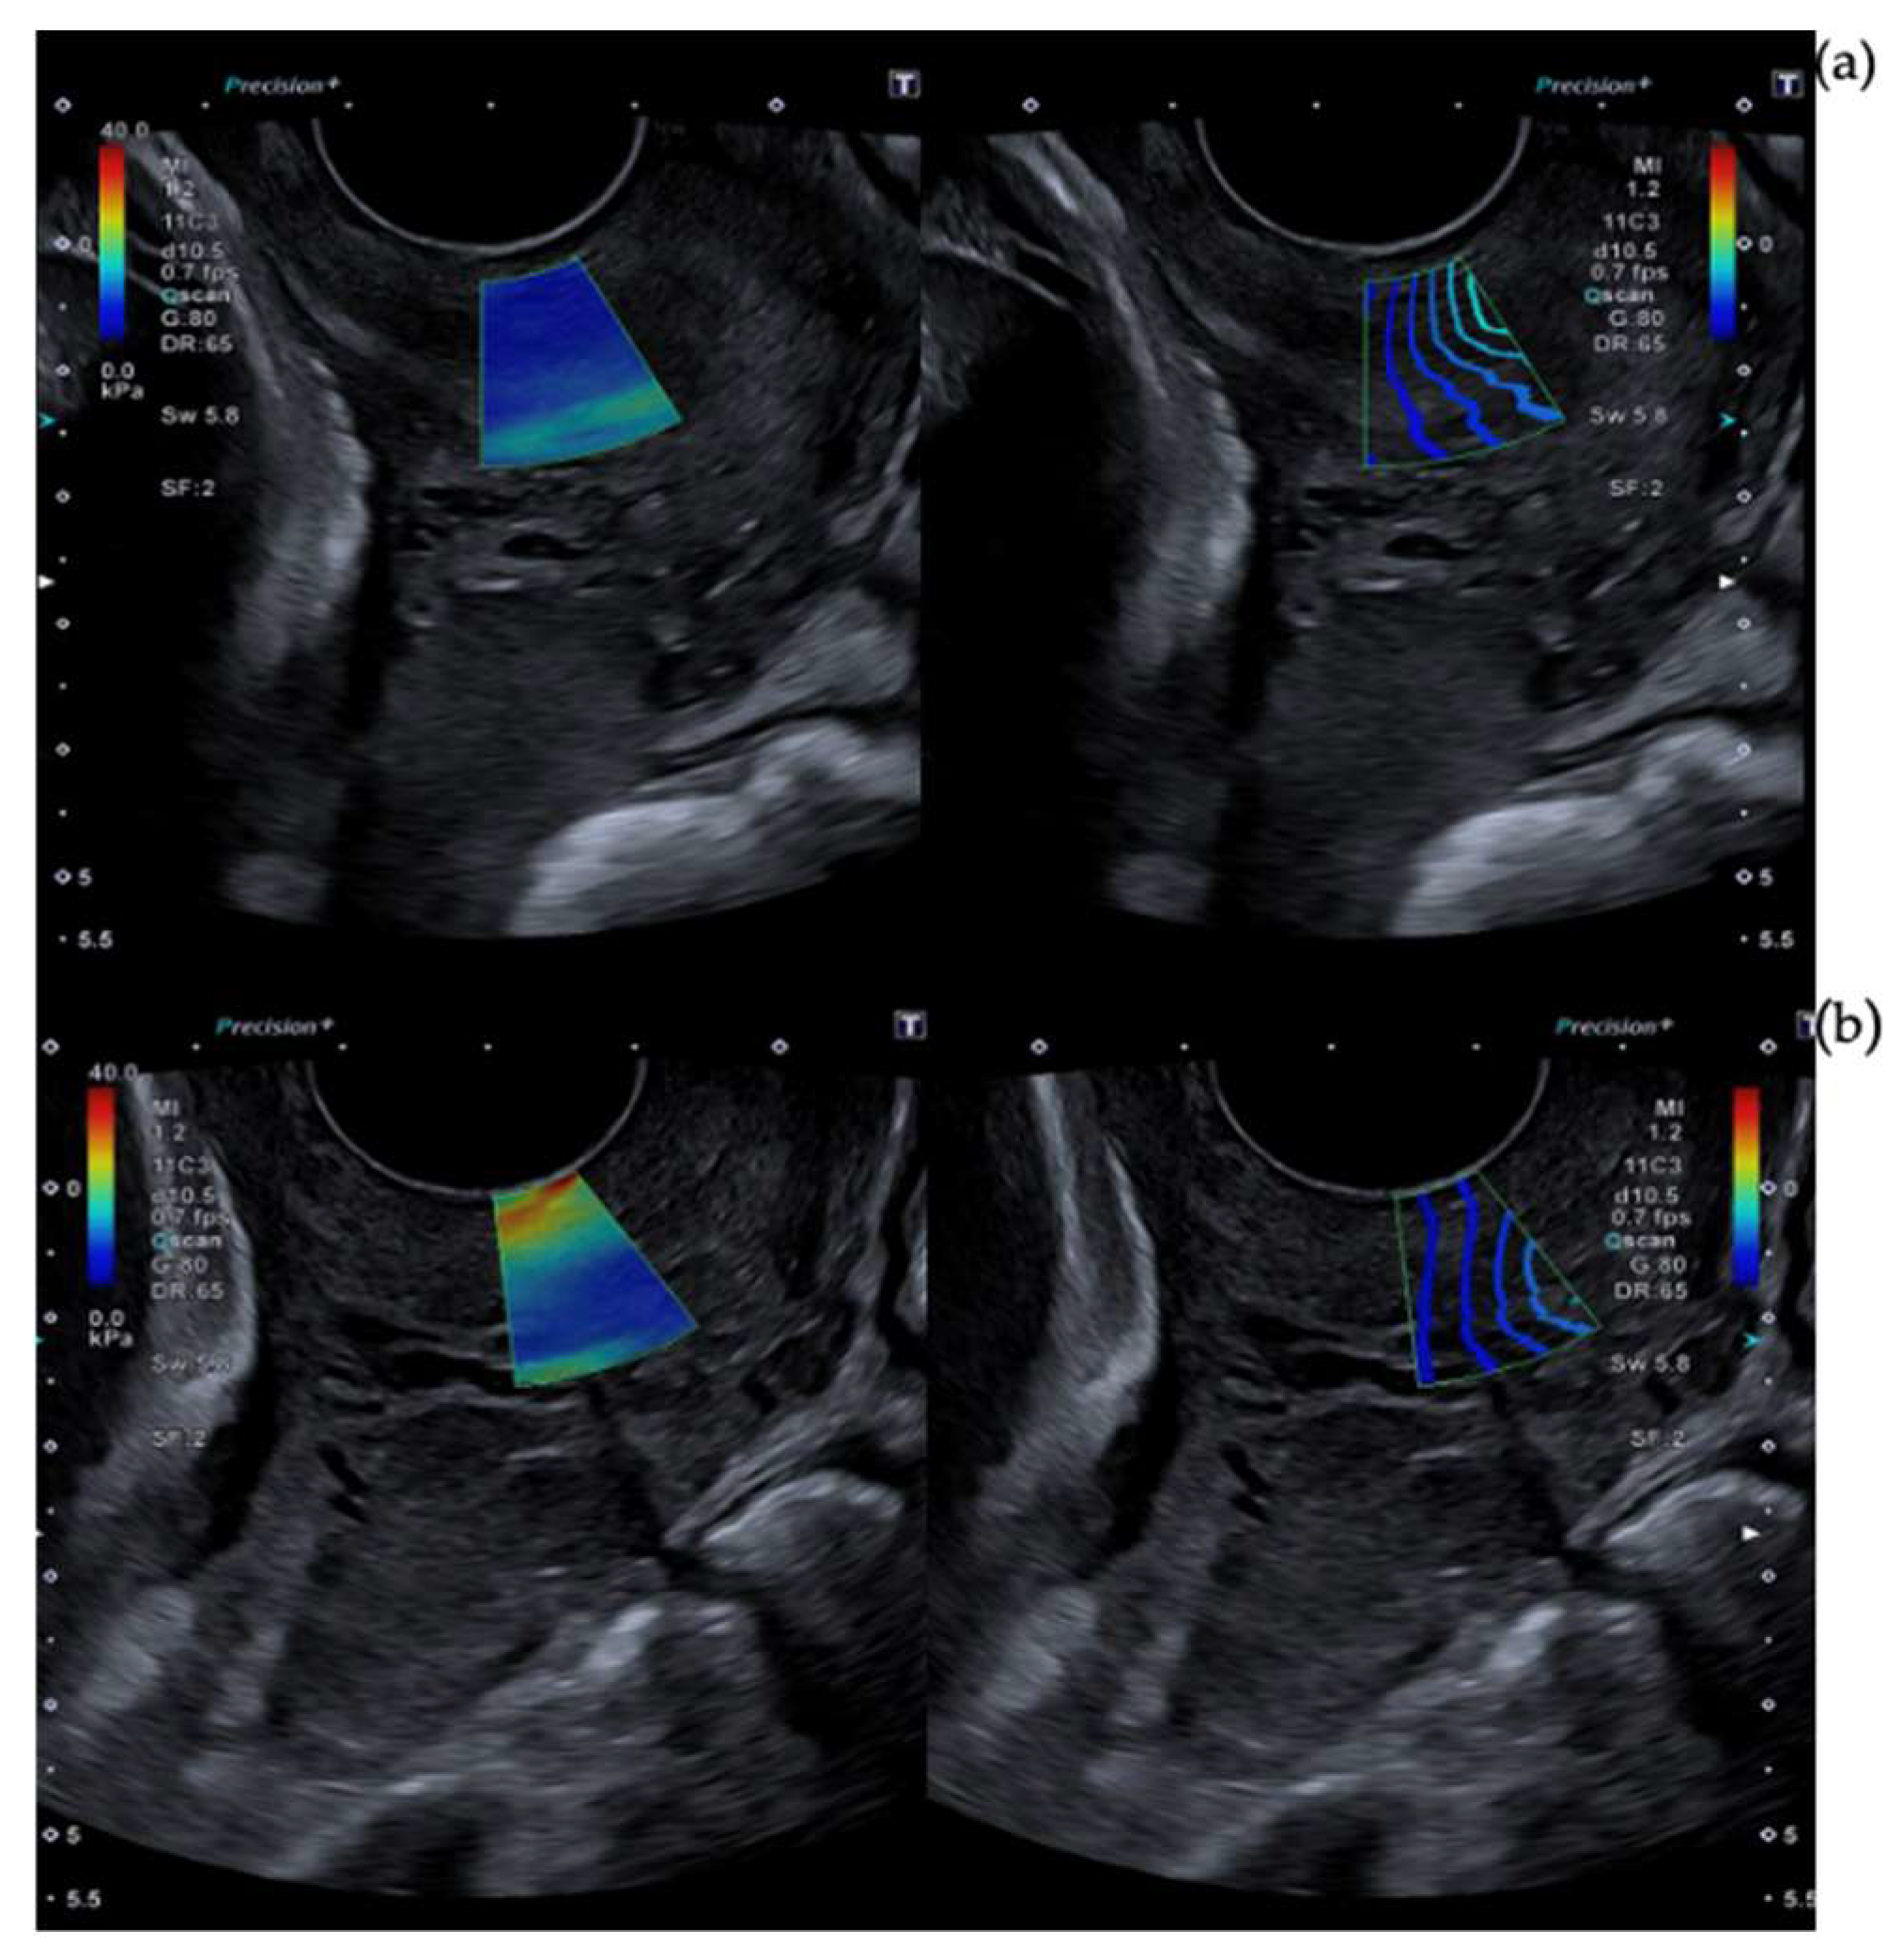

2.3. Cervical Shear Wave Elastography Measurement

- O’Hara, S.; Zelesco, M.; Sun, Z. Shear Wave Elastography on the Uterine Cervix: Technical Development for the Transvaginal Approach. J. Ultrasound Med. 2019, 38, 1049–1060. [Google Scholar] [CrossRef]

- Hernandez-Andrade, E.; Aurioles-Garibay, A.; Garcia, M.; Korzeniewski, S.J.; Schwartz, A.G.; Ahn, H.; Martinez-Varea, A.; Yeo, L.; Chaiworapongsa, T.; Hassan, S.S.; et al. Effect of depth on shear-wave elastography estimated in the internal and external cervical os during pregnancy. J. Perinat. Med. 2014, 42, 549–557. [Google Scholar] [CrossRef]

- Carlson, L.C.; Feltovich, H.; Palmeri, M.L.; Dahl, J.J.; Munoz Del Rio, A.; Hall, T.J. Estimation of shear wave speed in the human uterine cervix. Ultrasound Obs. Gynecol. 2014, 43, 452–458. [Google Scholar] [CrossRef]